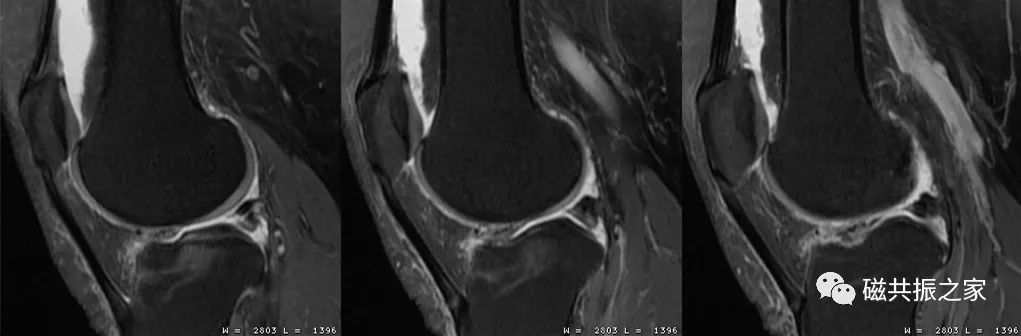

在进行四肢关节的扫描摆位时,首先要让被检者处于最为舒适的状态才能顺利地完成整个检查,特别是对于一些比较特殊的被检者。如上图△,对于该呈90°的肘关节的扫描,我们需要考虑选择何种线圈,被检者处于何种体位才能获得比较理想的图像质量。

如上图△,图像中三角区域类型水肿信号的表现,其很容易被误诊;重新摆位后下图▽。

图像中局部区域的“水肿”信号消失。实践告诉我们,在四肢关节的扫描中,绝大多数的伪影都是由于摆位不合理造成的。